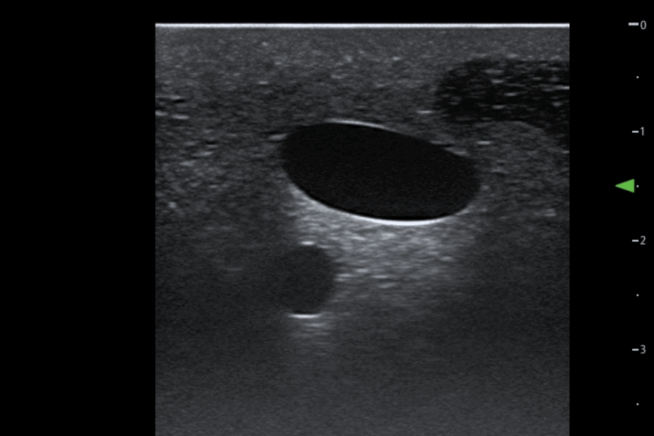

The TruUltra material is unlike anything else in the market. It showcases a high-quality ultrasound image to provide trainees with a true-to-life ultrasound training solution. Learners will benefit from realistic visualisation of the internal jugular and subclavian veins, carotid and subclavian arteries.

Poor quality ultrasound images are caused by air inside the blood. To improve the image, insert more blood into the jugular, subclavian, common carotid. Approximately 50ml (veins) and 20ml (arteries) should be sufficient.

The ultrasound insert facilitates 40+ full catheter incisions (20+ full insertions per site – Jugular vein & Subclavian Vein) using the recommended equipment sizes and 1000+ needle penetrations.